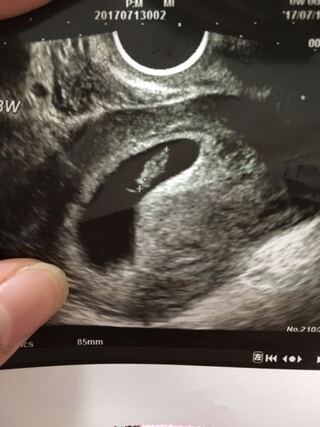

妊娠8週4日 8w4d の超音波 エコー 写真